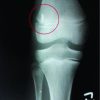

Full-length plain spine radiographs revealed regional kyphosis from C4 to C6 measuring 50°, but a normal SVA (Fig. 1). There was 3mm of anterolisthesis of C4 on C5, bony ankylosis of C5/6 at the disc level and posteriorly at the facets. Cervical CT confirmed the sagittal cervical malalignment and fusion of the C5/6 level. Cervical magnetic resonance imaging revealed multilevel cervical disc degeneration, focal kyphosis in the mid-cervicalspine, and mild-to-moderate central stenosis (worst at C4/5) and multilevel mild foraminal stenosis.